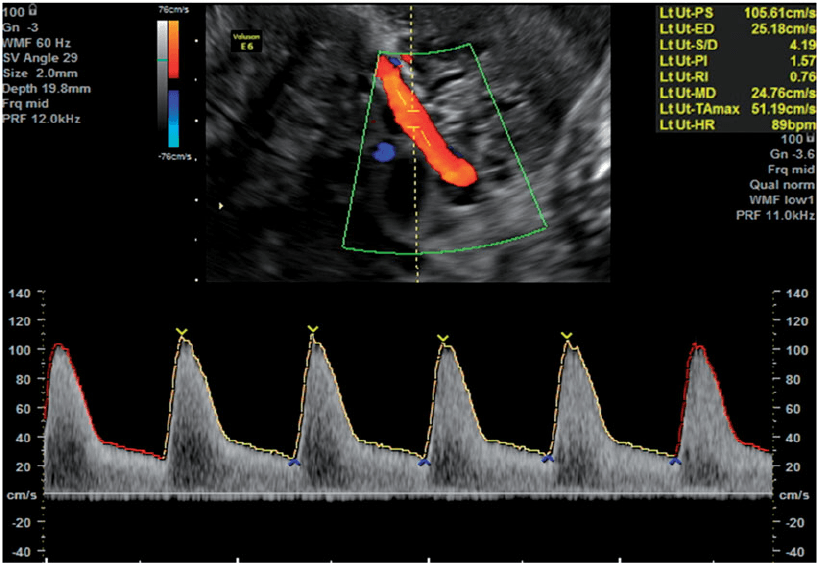

• Uterine Artery Doppler

• Gimdos arterijos Doplerio matavimas.